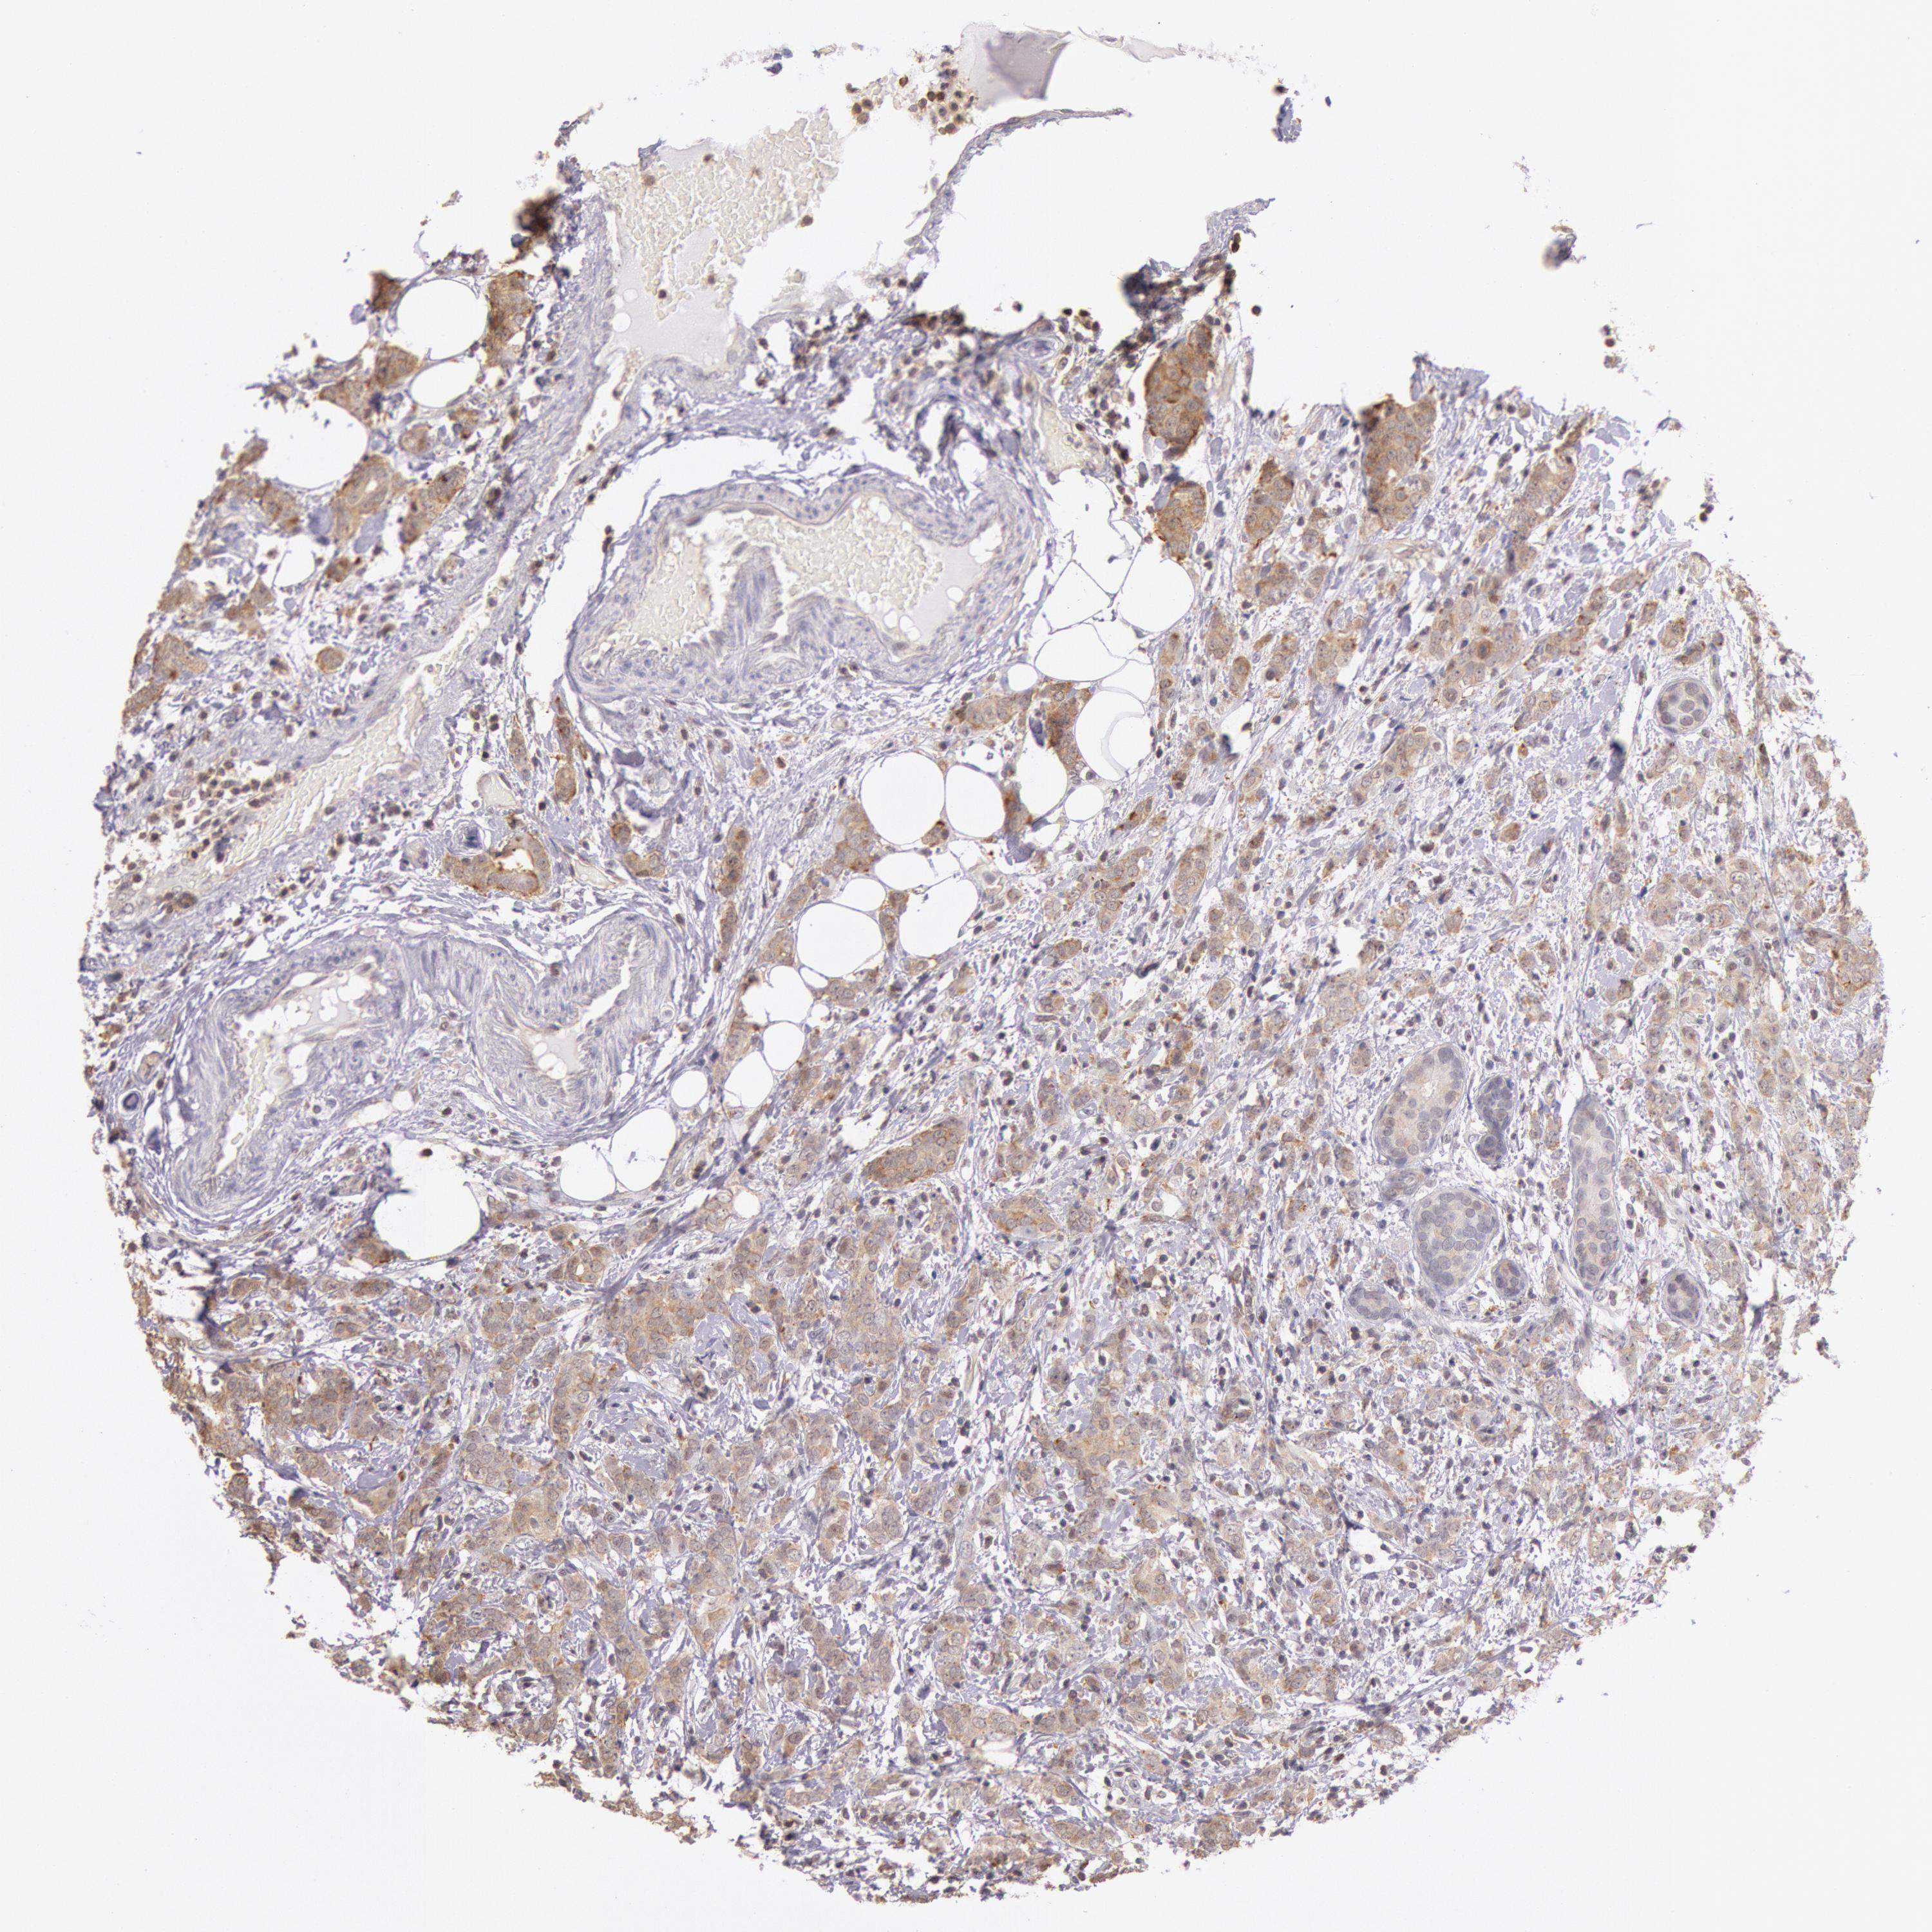

CANCER BREAST CANCER Show tissue menu

BRCA TCGA BRCA VALIDATION PROTEIN EXPRESSION